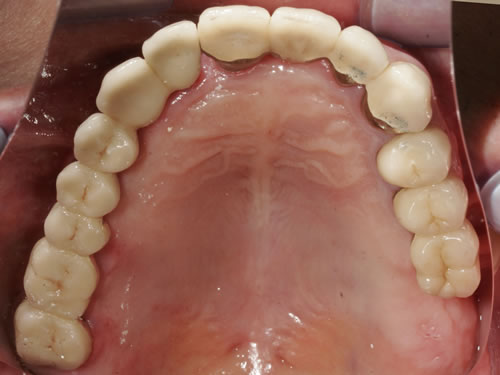

Bei dieser Ausgangssituation kann nicht in allen Fällen durch den Einsatz von Implantaten geholfen werden. Im Oberkiefer ist die Knochensituation meist ungünstiger als im Unterkiefer. Wenn allerdings ausreichend Knochen vorhanden ist oder geschaffen werden kann, lässt sich durch die Einpflanzung einiger Pfeiler die Prothese erheblich verkleinern und in Einzelfällen sogar eine Brücke anfertigen. Der Zahnersatz kann dann ohne jeden Würgereiz getragen werden (Abb. 3.15 bis 3.18).

Abb. 3.15: Zahnloser Oberkiefer mit sieben Implantaten versorgt.

Abb. 3.16: Eingeschraubte Unterkonstruktion zur Befestigung des zahntragenden Anteils.

Abb. 3.17: Eingesetzte herausnehmbare, gaumenfreie Brücke.